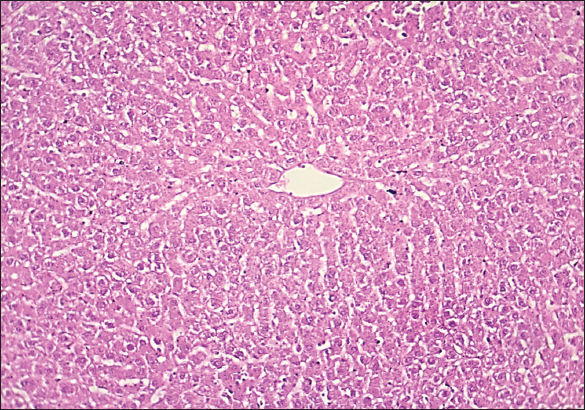

Fig. 1. Histological section of liver in rats of the control group. The section shows a normal histological structure for the hepatic sinusoid without any significant occupied lesion (H and E stain 100X).